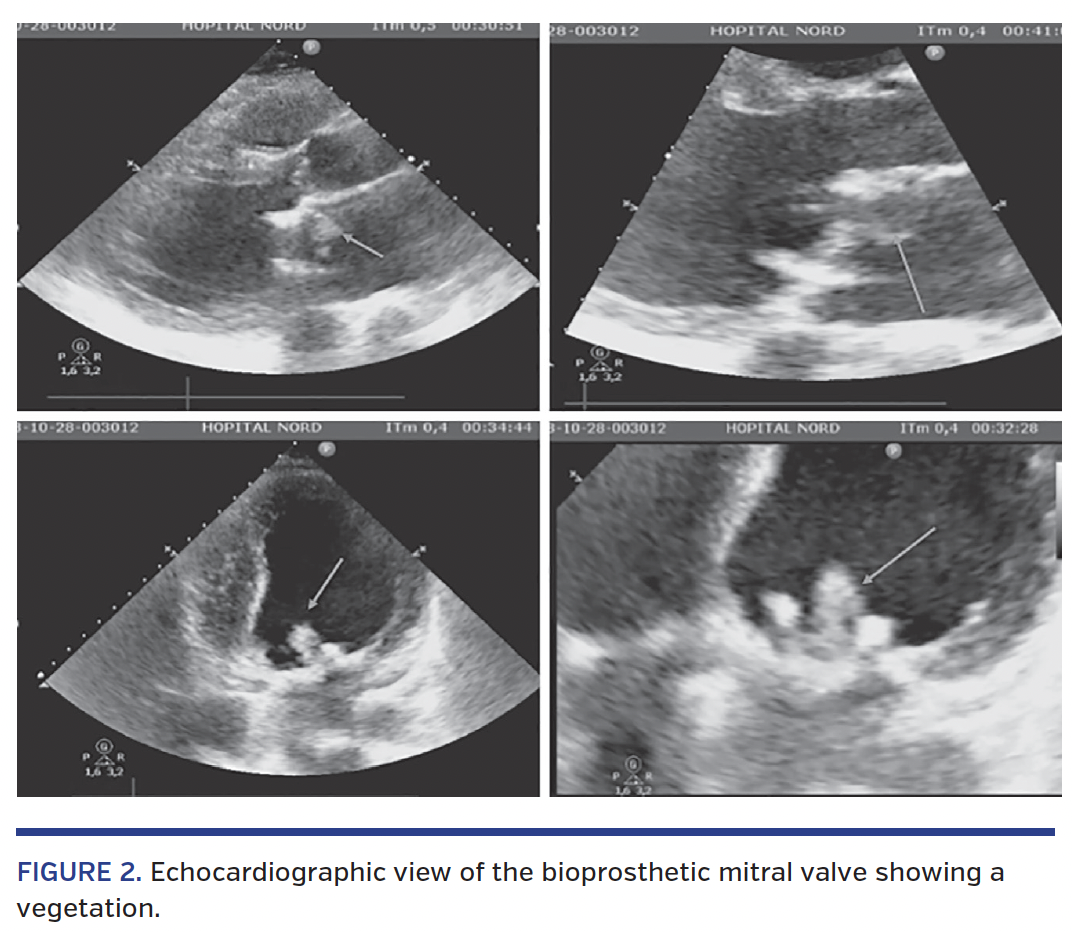

Angiographic study showed an occlusion of the circumflex artery on a bifurcation site with a marginal branch (Figure 3A). A 0.014˝ Balance Middleweight guidewire (Abbott Vascular) was used and coronary aspiration in both the marginal and circumflex branches with a 7 Fr Export aspiration catheter (Medtronic) was performed via the guiding catheter, which allowed embolic debris to be removed (Figure 3B). After repeated aspiration attempts, we observed TIMI 2 flow restoration in the marginal branch with a persistent occlusion of the circumflex artery. Kissing-balloon inflation with two 3.0 x 20 mm Ryujin Plus RX semicompliant balloons (Terumo) was use to restore complete revascularization of the circumflex coronary territory (Figures 3C and 3D). Histological examination of the debris (Figure 4) concluded that it was a part of the vegetation that had embolized.